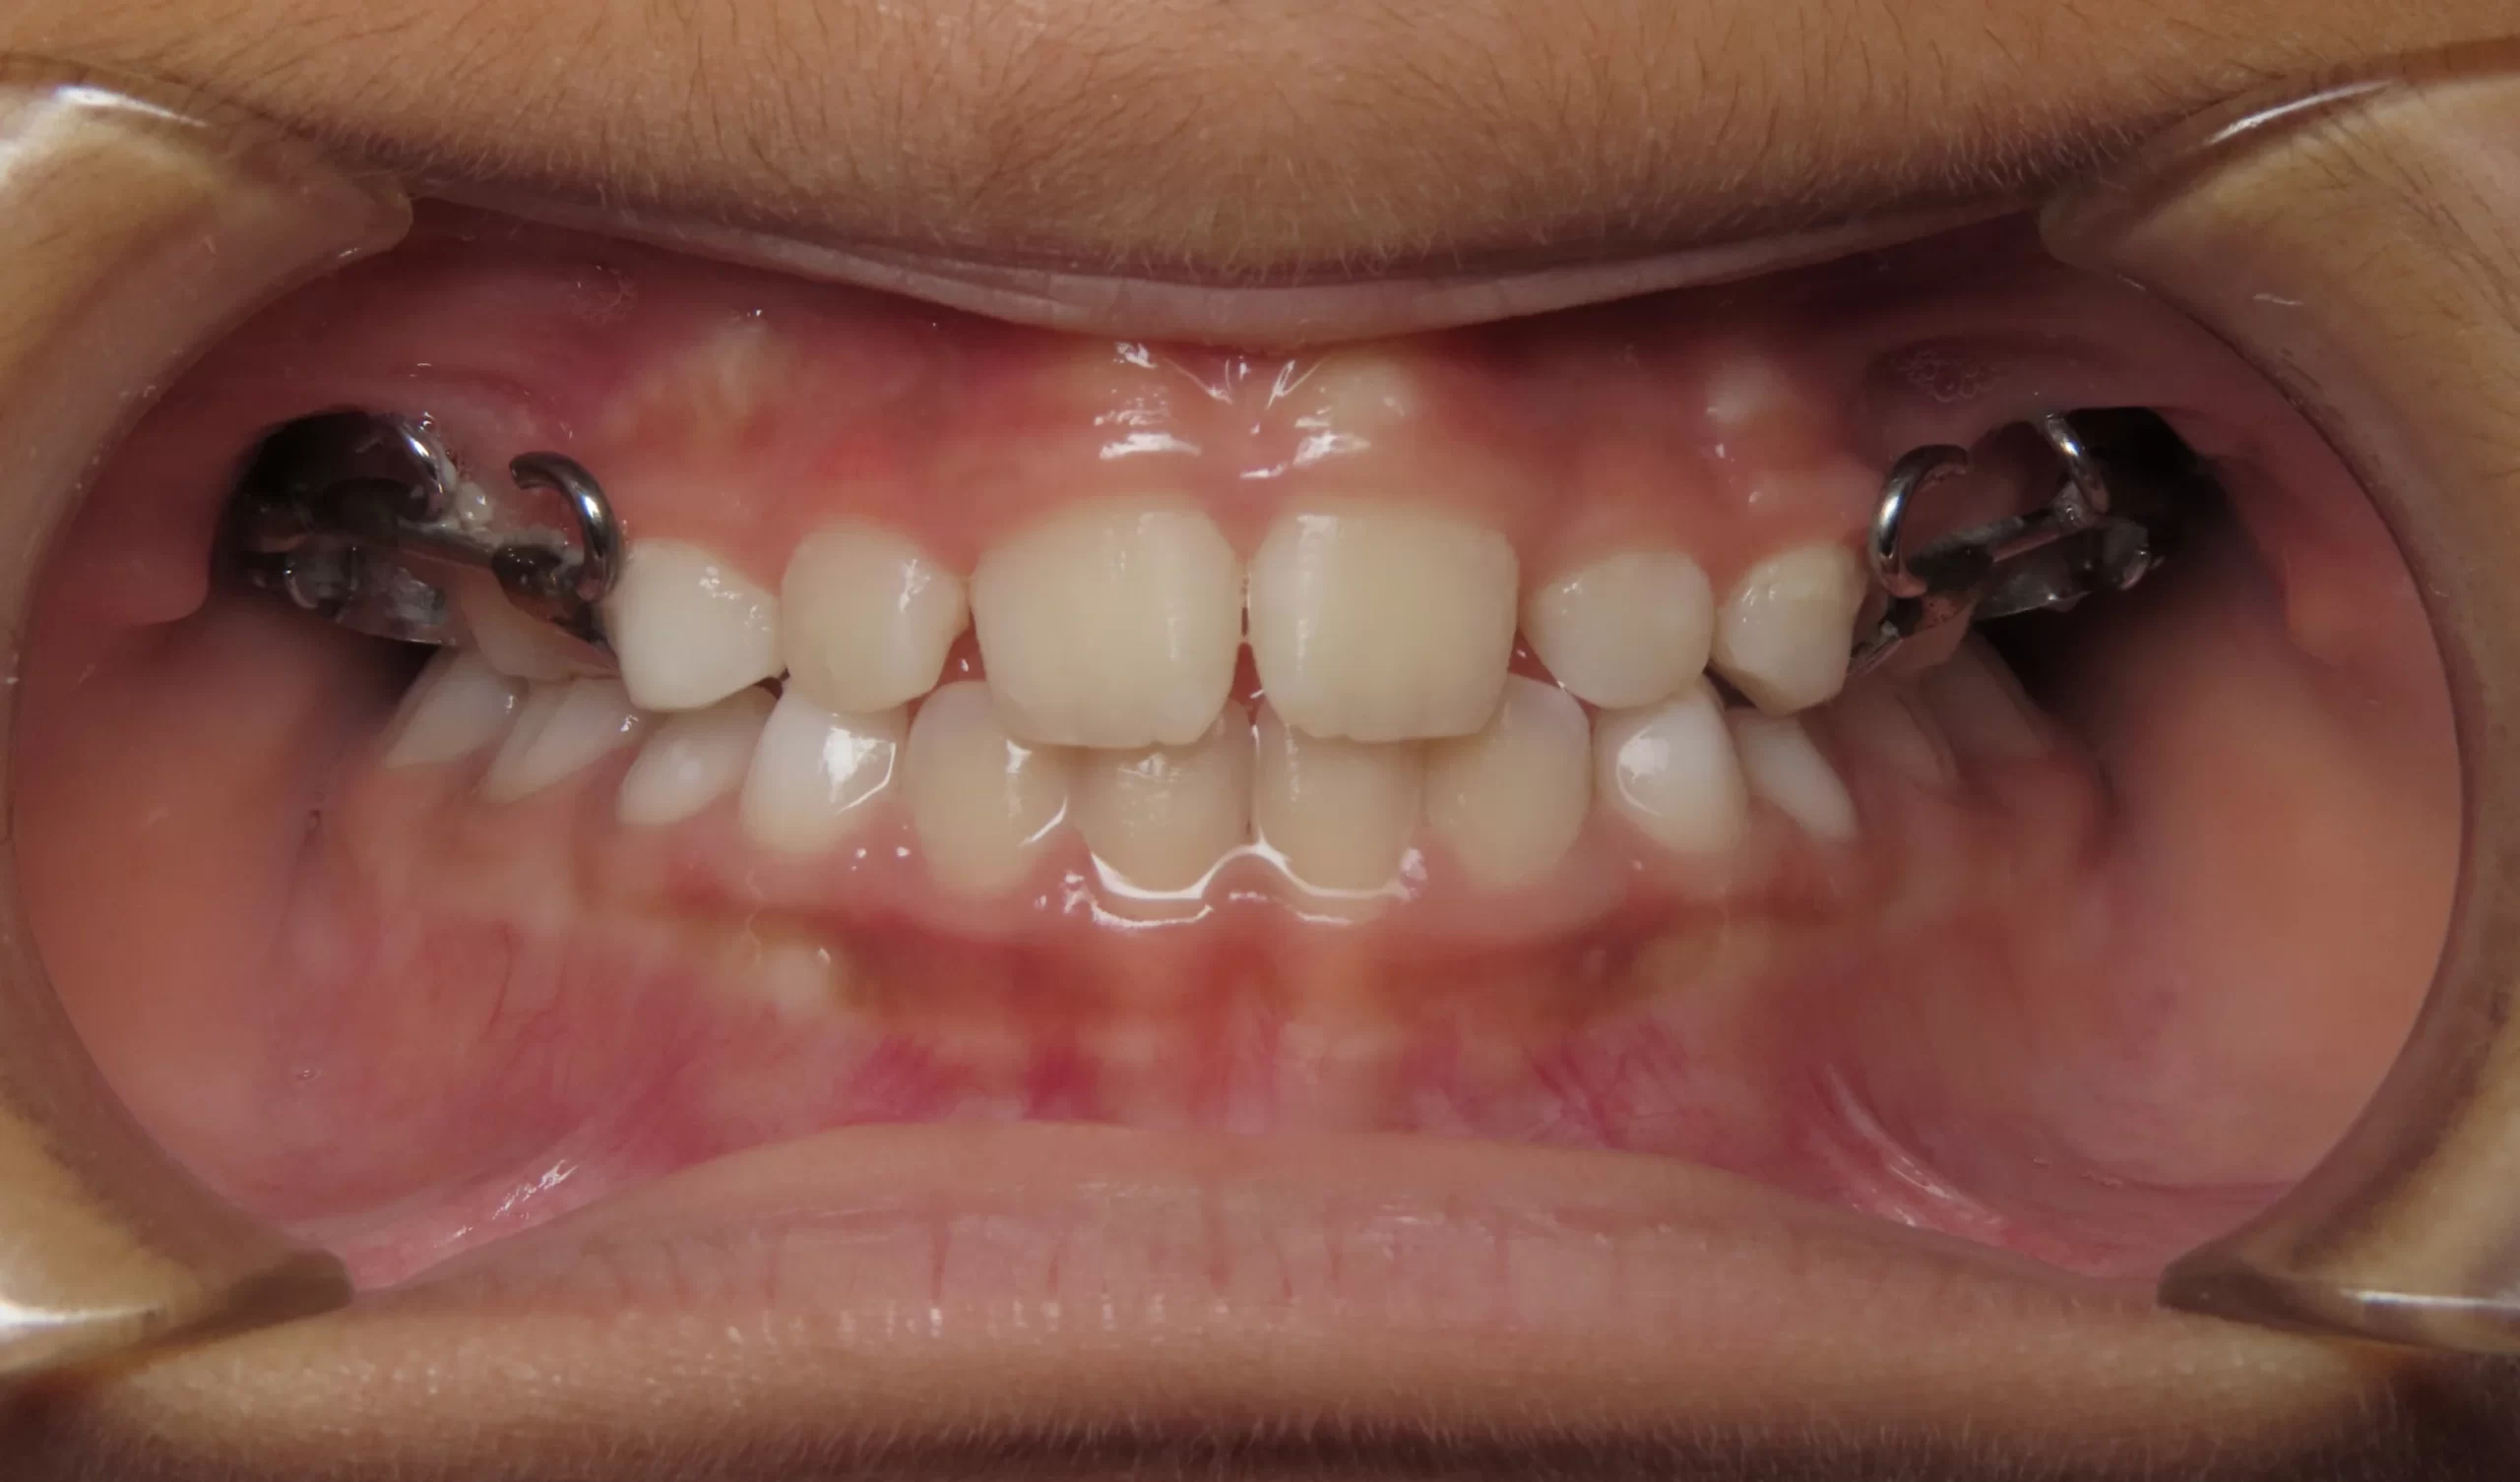

Patient treated with EXPANSION and braces

Before

After